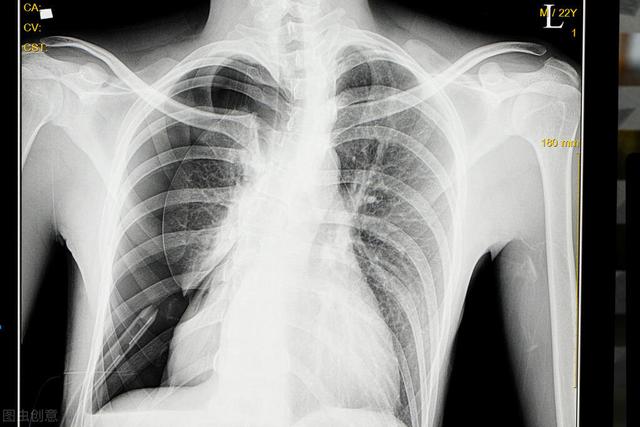

2、气胸

气胸,即气体进入了胸膜腔造成的疾病。它主要与胸部、肺部损伤有关。

气胸发生时,患者常常会感到突然的胸痛。与此同时,很多患者还会出现胸口发闷,有刺激性的咳嗽。还有少部分患者会出现刀割、针刺一般的异样感觉。

气胸多半发生在腹压剧烈变化时。例如举重、提重物、屏气排便、剧烈咳嗽时。此外,如果肺部组织病变出现破损,也可能导致这一问题。